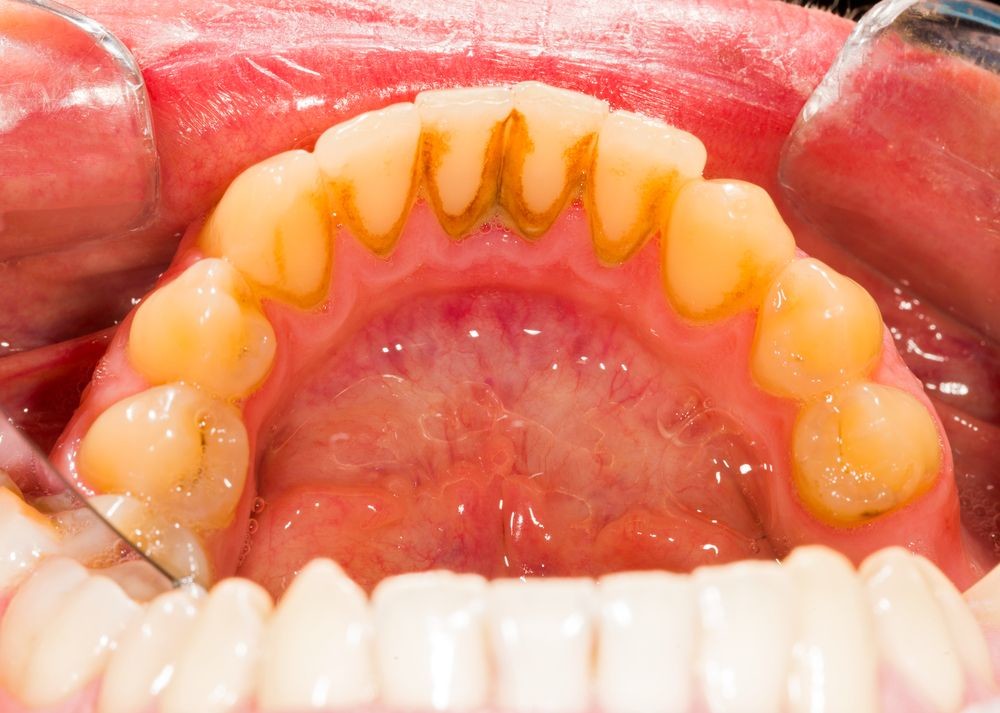

Do Wisdom teeth affect braces?

For those people who have wisdom teeth, they usually erupt in early adulthood. Wisdom teeth may cause dental issues like overcrowding, especially if they’re impacted. However, many people have plenty of room for their wisdom teeth and they have no problems with them.

Like previously stated, many people have their wisdom teeth come in with no problems. The teeth grow in straight and don’t affect the person’s bite. So overall, no, wisdom teeth do not cause significant overcrowding in the front of the mouth or severely disrupt any progress that was made with dental work like braces.

However, if they do not come in correctly or if a person’s jaw simply doesn’t have room for the new teeth, they can cause overcrowding among the back teeth.

While wisdom teeth may not necessarily cause a major issue with the dental progress that has been made with braces, there may still be reasons to have a wisdom tooth extraction. There are many wisdom tooth concerns that may call for tooth removal surgery, including: Crowding of back teeth, Infected gums, Bone defects, Root resorption, Dental diseases.

If a wisdom tooth becomes impacted or doesn’t erupt straight up, this can cause significant problems for the person. While some people may experience absolutely no problems with their wisdom teeth or get lucky enough to not have any of these extra molars at all, others may experience problems with them.